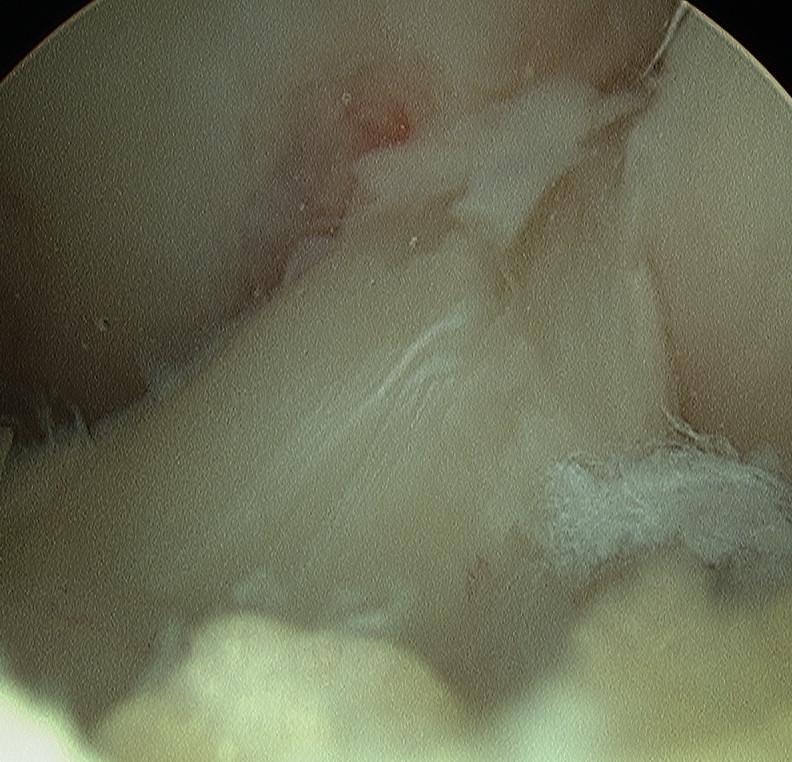

Partial Tears

- provide a LARS scaphold for the injured ACL to heal onto

- the LARS has a specifice portion designed to be inside the native ACL